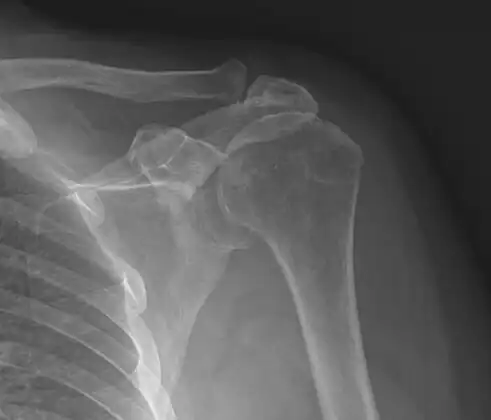

Imaging

Plain x-rays of the shoulder can be used to detect some joint pathology and variations in the bones, including acromioclavicular arthritis, variations in the acromion, and calcification. However, x-rays do not allow visualization of soft tissue and thus hold a low diagnostic value.[5] Ultrasonography, arthrography and MRI can be used to detect rotator cuff muscle pathology. MRI is the best imaging test prior to arthroscopic surgery.[5] Due to lack of understanding of the pathoaetiology, and lack of diagnostic accuracy in the assessment process by many physicians,[21] several opinions are recommended before intervention.